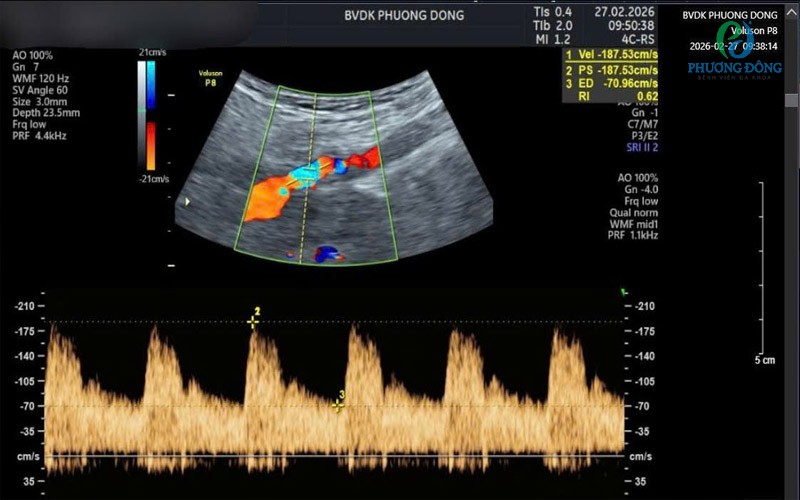

Bệnh nhân có mảng xơ vữa gây hẹp đáng kể động mạch cảnh khiến dòng máu phụt mạnh khi đi qua chỗ hẹp được thăm khám tại bệnh viện đa khoa Phương ĐôngBệnh nhân có mảng xơ vữa gây hẹp đáng kể động mạch cảnh khiến dòng máu phụt mạnh khi đi qua chỗ hẹp được thăm khám tại bệnh viện đa khoa Phương Đông